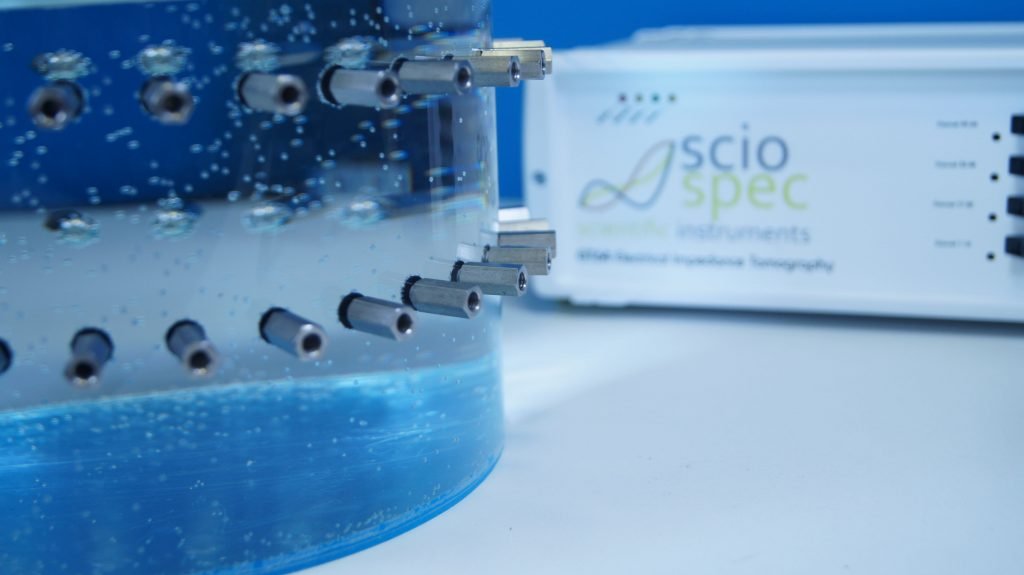

The study was validated through experimental data using the Sciospec EIT32 impedance tomography system, demonstrating a powerful synergy between computational modeling and real-world measurement accuracy. This article explores the solver’s key innovations and how advanced measurement solutions enabled high-fidelity imaging in both research and potential clinical applications. At the core of this success is Sciospec’s scalable, high-precision measurement technology.

At the heart of the experimental validation was Sciospec’s EIT32 system, which provided the high-fidelity voltage measurements required for the SRL-EII solver to operate effectively.

In essence, the EIT32 system served not merely as a measurement tool, but as a critical enabler of this innovation process. Its seamless integration into the experimental workflow highlights how advanced impedance tomography systems can accelerate progress in electrical impedance imaging from data acquisition to high-precision computational modelling

The EIT32 system’s design directly supported the high performance and accuracy demonstrated in the SRL-EII solver. These standout features made it a critical enabler for the research:

🔍 High-Fidelity Data : Ensure minimal noise with coaxial cabling and ultra-precise voltage acquisition.